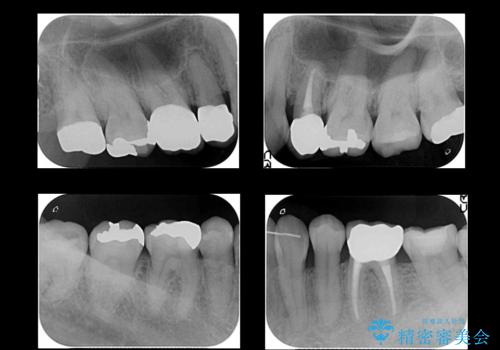

左下6番、左上4番は失活していたため、根管治療を行っています。

右上7・左上6:PGAインレー

右上8:PGAクラウン

左上4・左下6・右上56:ジルコニアクラウン

左上7・左下7:emaxインレー

での治療を行っています。

根管治療はDr.大元が行っています。